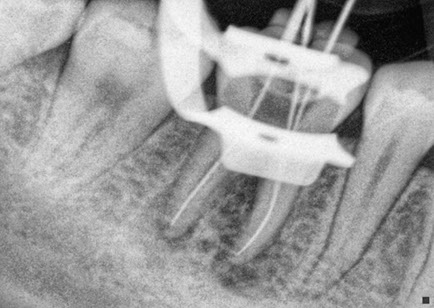

During the root canal treatment, the nerve and the pulp are eliminated and the tooth gets cleaned inside, the root is filled with the correct materials and the next step is the reconstruction of the dental crown. All this treatment is performed by applying local anesthesia, the same anesthesia that is used in a common procedure.

The root canal treatment gives you more lifetime of usage to your dental piece. At Dental Evolution Cancun we recommend avoiding the extraction of your dental piece, instead, you can choose this treatment and we promise you it’s a painless procedure; due to the cutting edge technology, rotating instrumental, ultrasound system, and to our “digital radiographs” that all performs a crucial role in the root canal process as well as our expert crew who will look after you with the professionalism that we always provide.